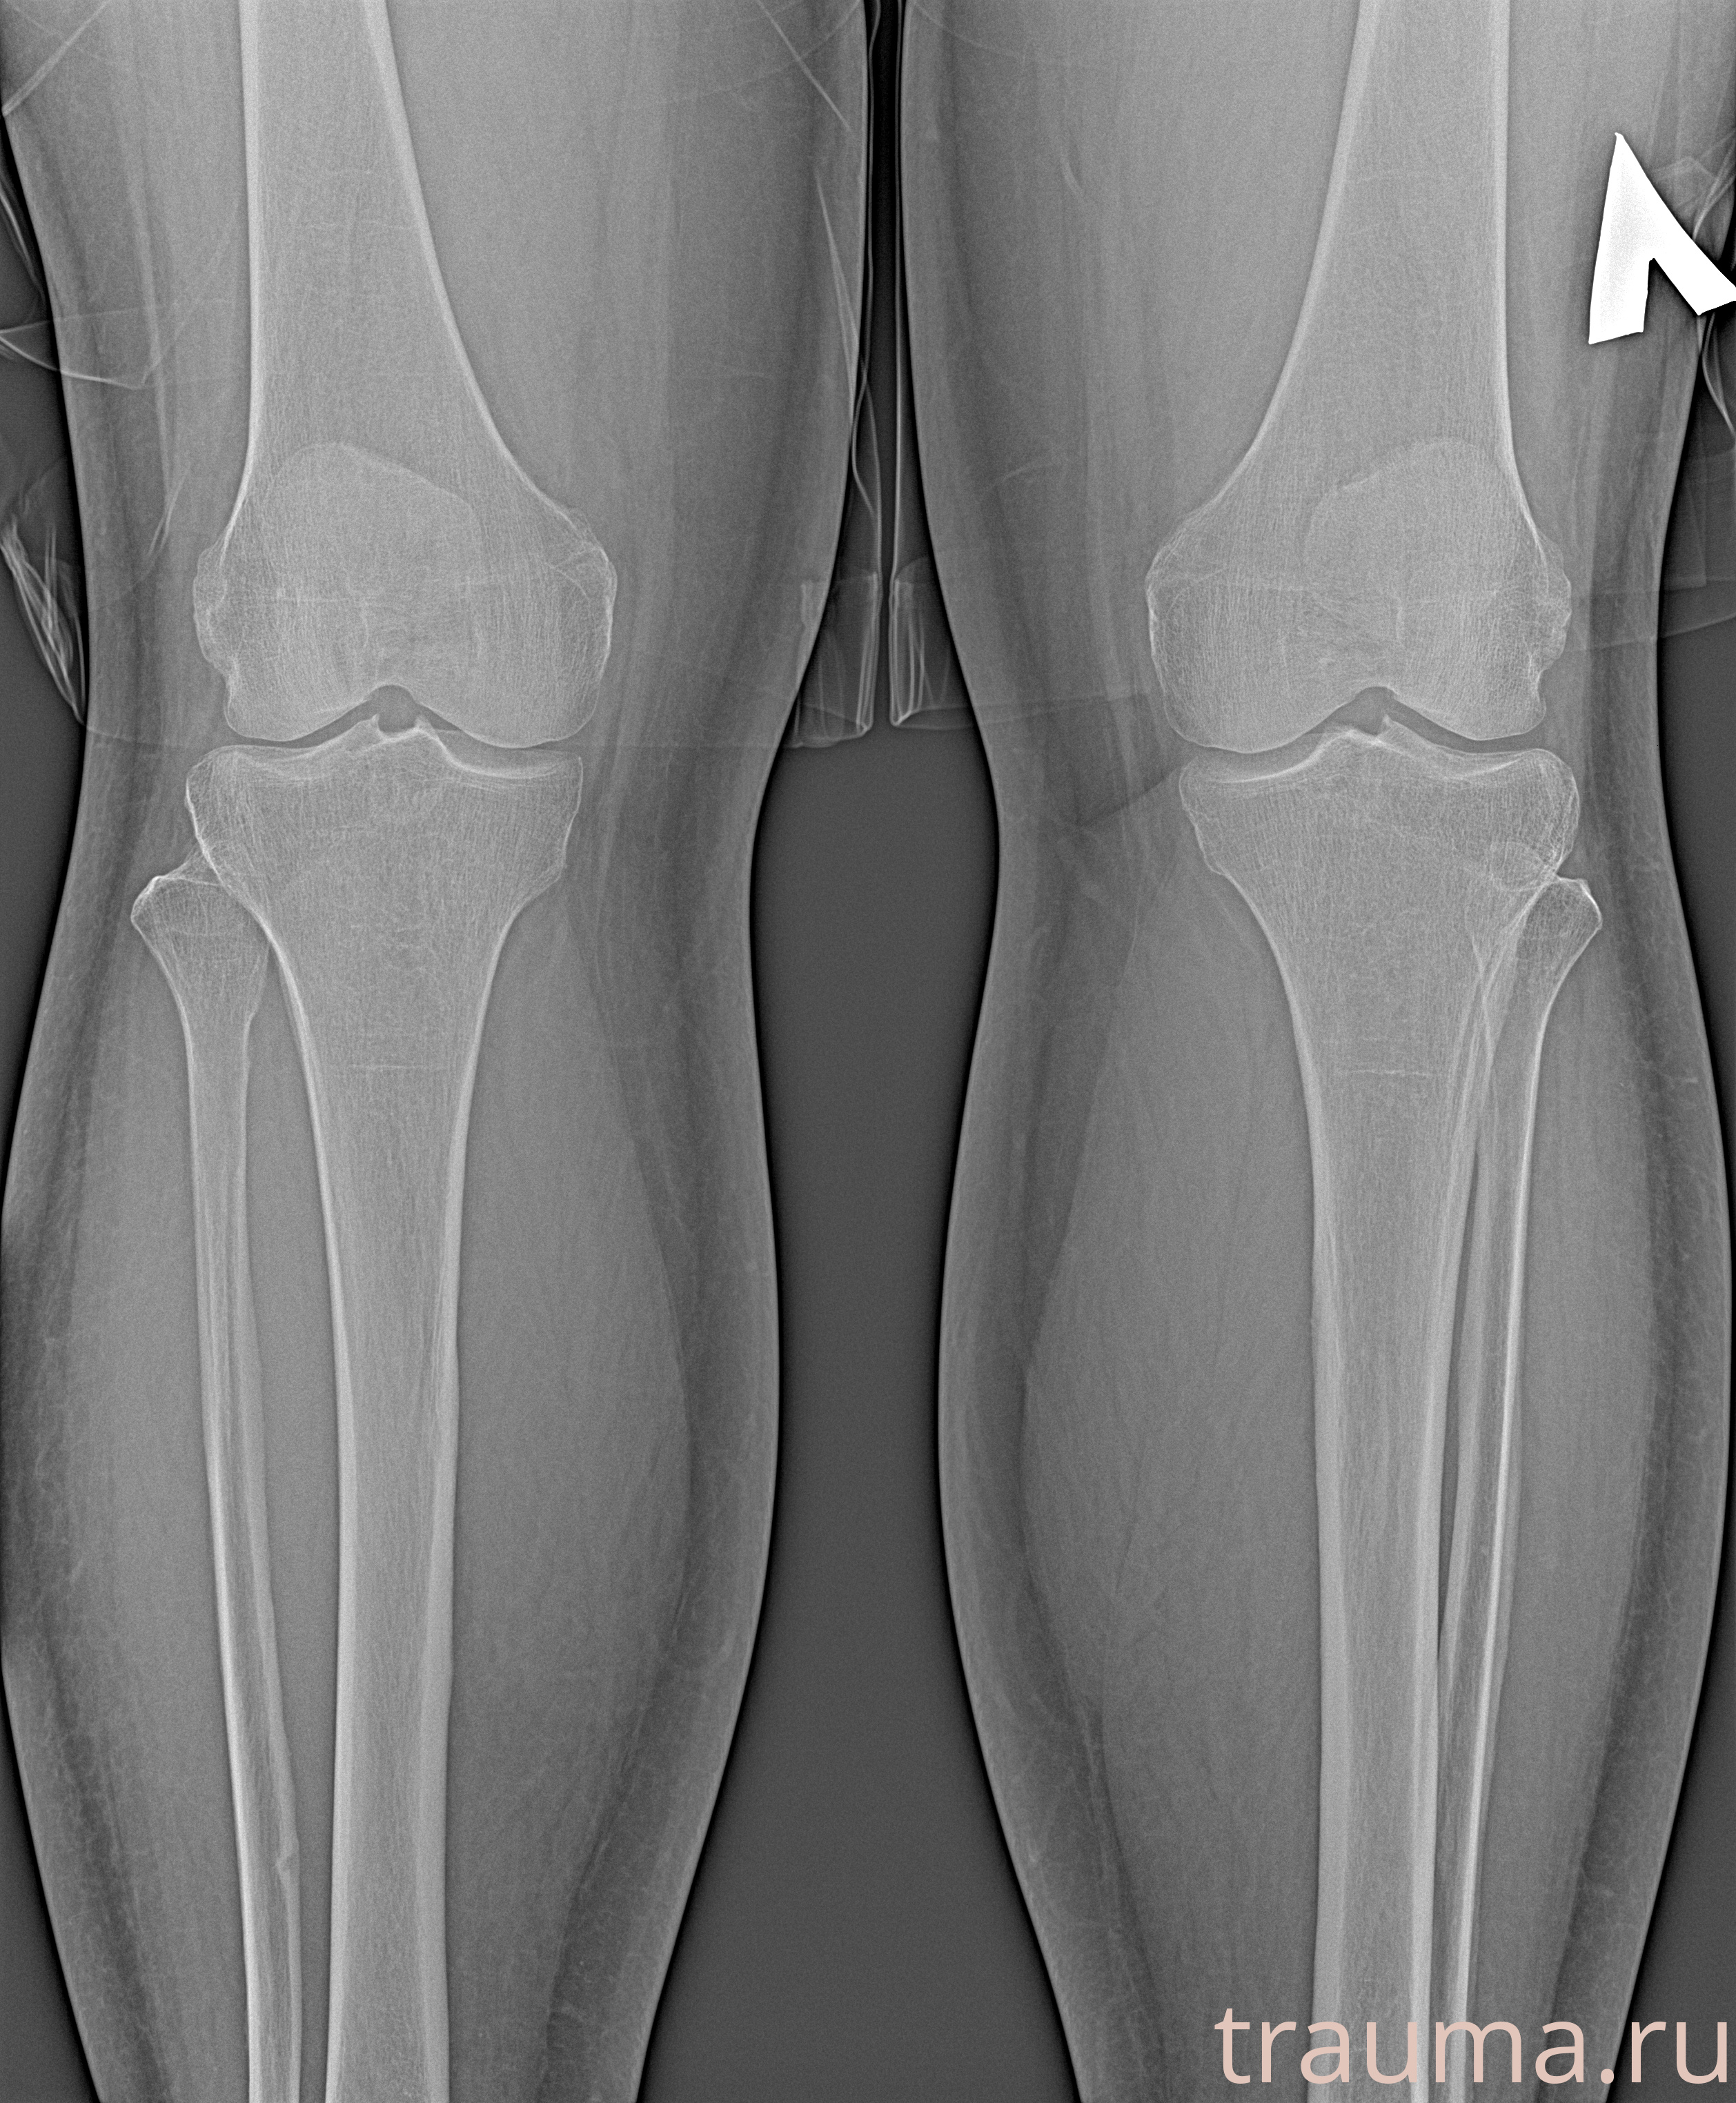

Рентген на дому: по вашему адресу приезжает врач-рентгенолог, травматолог-ортопед с мобильным рентгеновским аппаратом, проводит диагностику травмы или заболевания, делает необходимые рентгенограммы, дает рекомендации по дальнейшему лечению. Получить качественные снимки в домашних условиях возможно благодаря уникальной методике, разработанной МосРентген Центром для института  Склифосовского